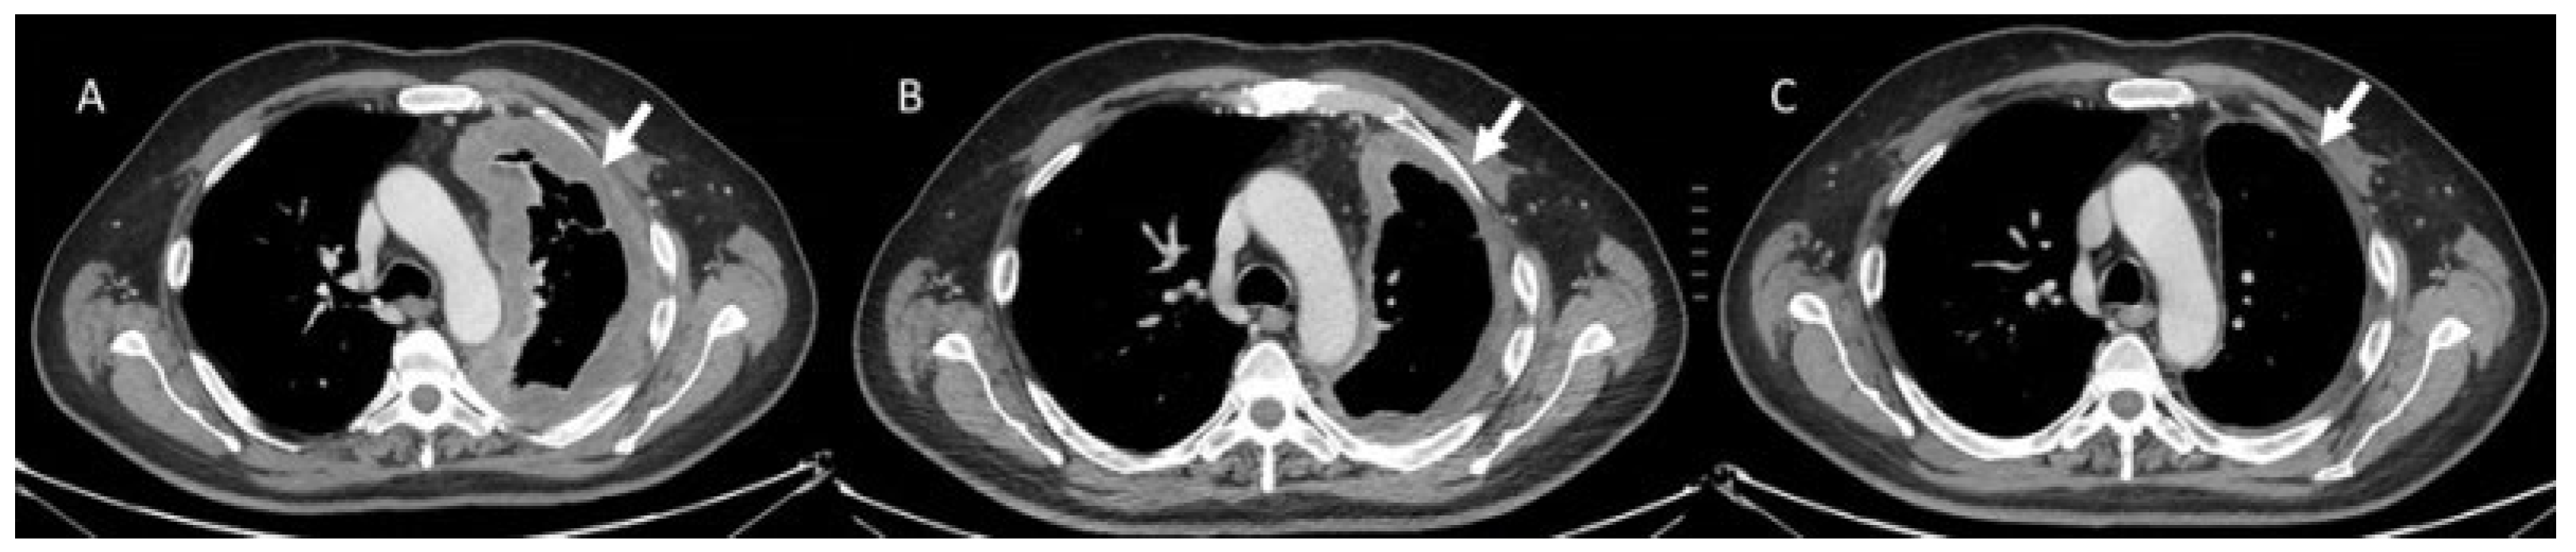

- Kalisz, K.R.; Ramaiya, N.H.; Laukamp, K.R.; Gupta, A. Immune Checkpoint Inhibitor Therapy-related Pneumonitis: Patterns and Management. Radiographics 2019, 39, 1923–1937. [Google Scholar] [CrossRef] [PubMed]

- Wang, G.X.; Kurra, V.; Gainor, J.F.; Sullivan, R.J.; Flaherty, K.T.; Lee, S.I.; Fintelmann, F.J. Immune Checkpoint Inhibitor Cancer Therapy: Spectrum of Imaging Findings. Radiographics 2017, 37, 2132–2144. [Google Scholar] [CrossRef]

- Kwak, J.J.; Tirumani, S.H.; Van den Abbeele, A.D.; Koo, P.J.; Jacene, H.A. Cancer immunotherapy: Imaging assessment of novel treatment response patterns and immune-related adverse events. Radiographics 2015, 35, 424–437. [Google Scholar] [CrossRef]